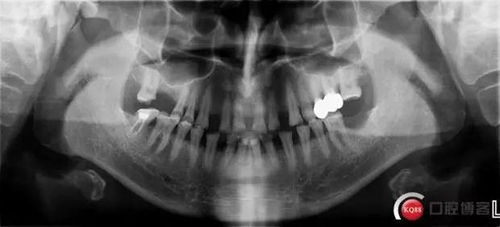

X線檢查:

CBCT檢查: